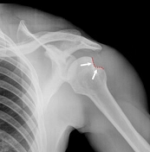

Acromio-clavicular joint injury

| Rockwood classification of injury | |

| Type I | • clavicle not elevated with respect to the acromion • all lig's intact |

| Type II | • clavicle elevated but not above the superior border of the acromion • AC lig and capsule ruptured |

| Type III | • clavicle elevated above superior border of acromion but coraco-clavicular distance <2x normal (ie <25mm) • all lig's and capsule ruptured • deltoid and trapezius M's detached |

| Type IV | • clavicle displaced posterior into trapezius • all lig's and capsule ruptured • deltoid and trapezius M's detached |

| Type V | • clavicle is markedly elevated and coraco-clavicular distance >2x normal (ie >25mm) |

| Type VI | • rare - clavicle inferiorly displaced behind coraco-brachialis & biceps tendons |

| Types IV, V, VI are effectively variants of Type III | |